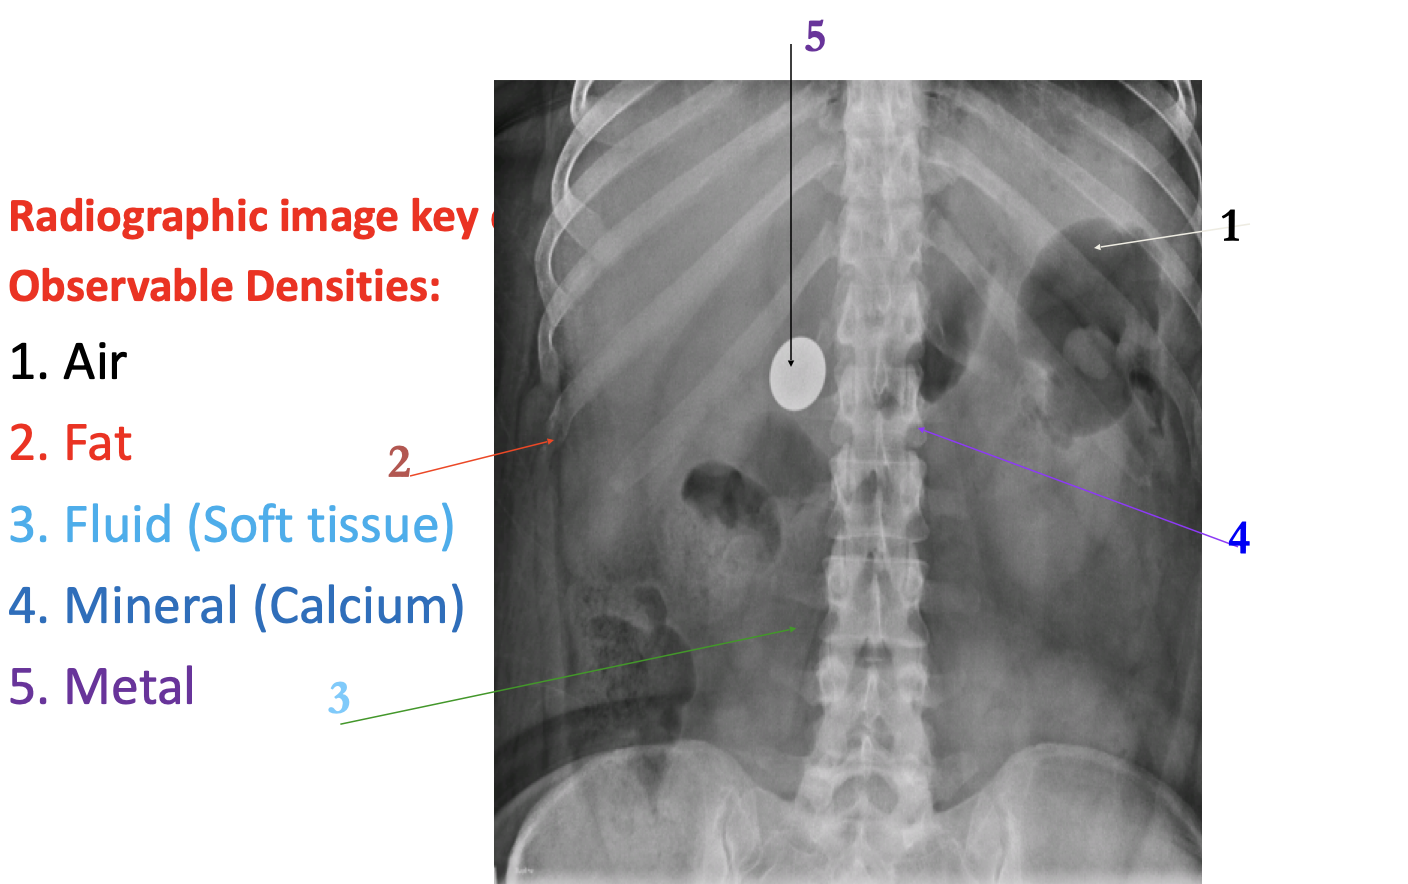

Technical Background There are 3 main parts involved to create an x-ray image:

Q: Where on this image have x-rays passed through the body to the greatest degree? Most: Lungs | Least: Bones